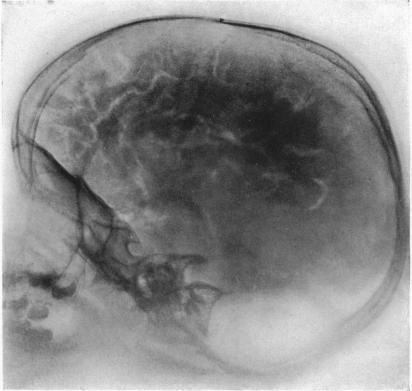

Before the advent of CT and MRI in the 1970s and 1980s, radiologic techniques for localization were invasive and uncomfortable: pneumoencephelography involved the draining of cerebrospinal fluid from the brain, and the injection of air or helium to fill the now-empty space in and around the brain. The patient was brought to get x-rays of the head, while moving their head in awkward orientations, often while suffering terrible headache and nausea. And even then, this modality could only ever offer a limited ability to see brain tumors. Good clinical examination still was necessary to localize sites of stroke, immunological lesion, or spinal cord pathology.

Image: “Photograph of a roentgenogram.” From Walter E. Dandy, “Roentgenography of the brain after the injection of air into the spinal canal.” Ann. Surg. 70, 4 (1919): 397-403. Accessed https://commons.wikimedia.org/wiki/File:Pneumoencephalography.jpg.